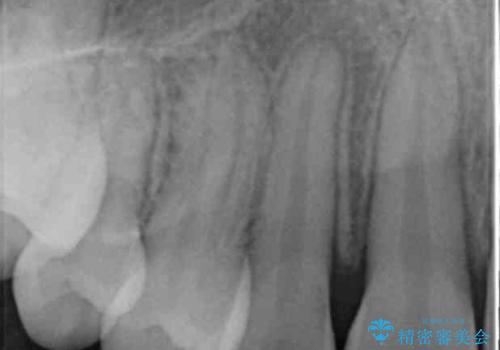

犬歯の両側の歯に関しては移動することにより歯槽骨が順調に回復し、上顎洞底の形態にかかわらず歯根のパラレリングを行うことができました。

犬歯の両側の歯に関しては移動することにより歯槽骨が順調に回復し、上顎洞底の形態にかかわらず歯根のパラレリングを行うことができた理由としては、年齢が10代前半と若かったからだと思います。

成人ですと、なかなかこういった柔軟な歯の移動は難しいことが多いです。

左上4−7については、近心傾斜をしていたため、右上3を抜かずに遠心に移動して非抜歯で治療を行う案も提案しましたが、抜歯を選択されました。結果的に深く埋まっていた右上犬歯を牽引せずにすみ、さらに歯根の向きも整えることができてよかったです。治療も比較的短期間で済みました。